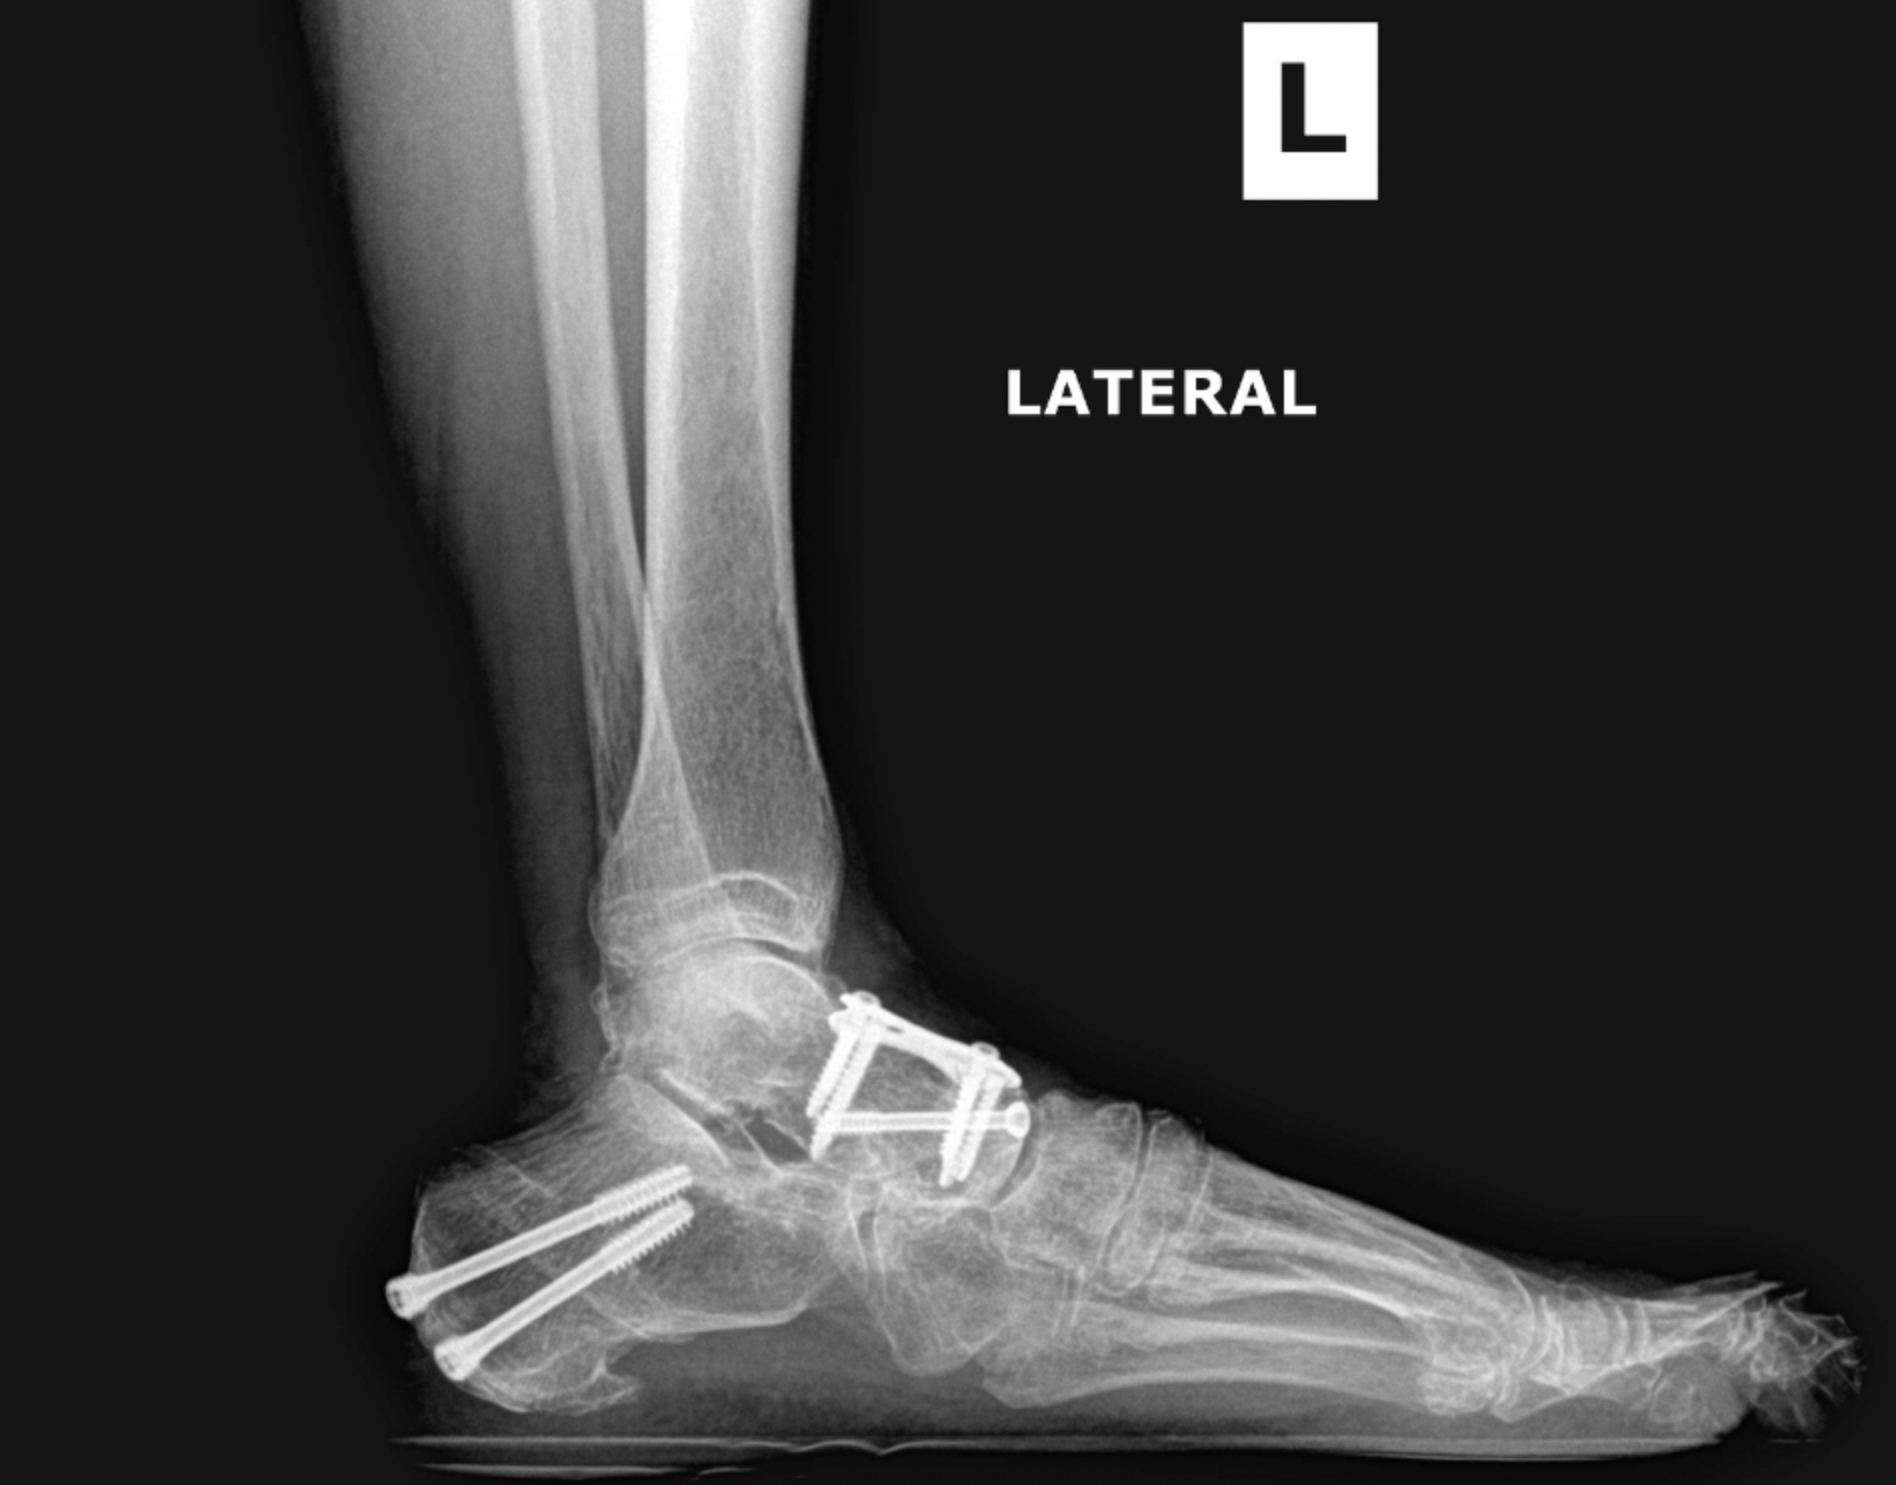

Ankle fracture repair

Pre-op XR Images

Postop XR Images